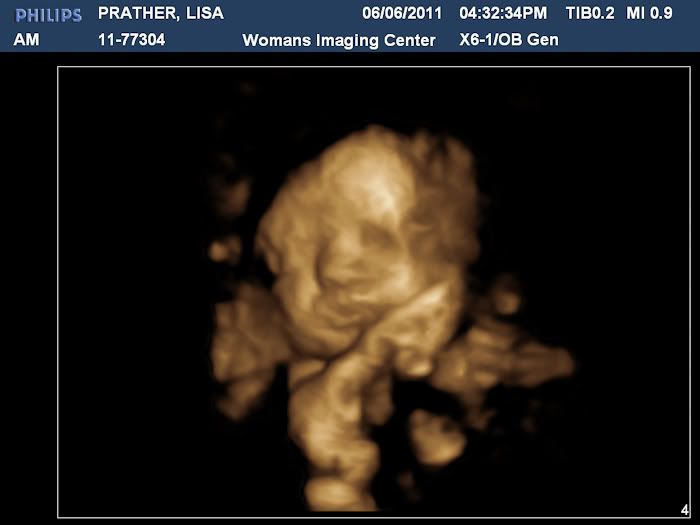

Here is his sweet face! I cried when I saw this. I think he is just precious!

Then we got to see some in 3D, which were amazing!

Stephen thinks he has my nose and I think he has my cubby cheeks! We both think he is just adorable and can't wait to meet him!